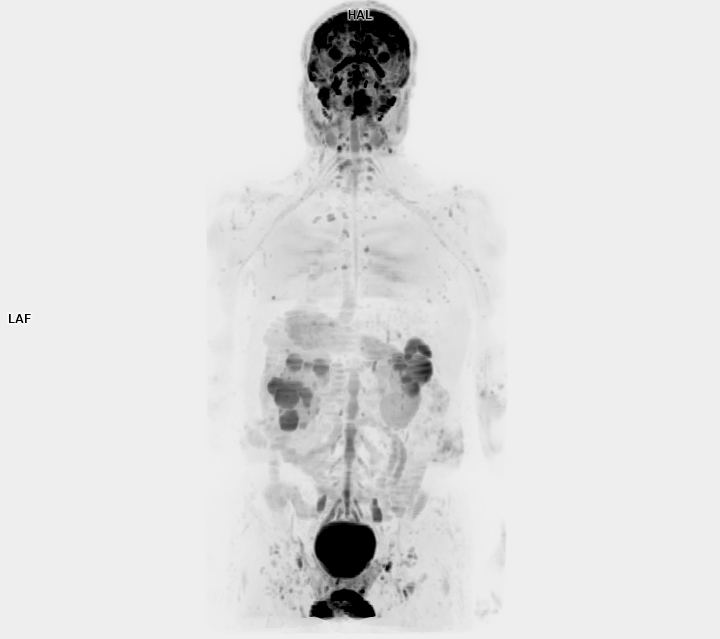

• 3 TESLA MR ÇEKİM GÖRÜNTÜLERİ

3 Tesla MR Çekim Görüntüleri

• 3 Tesla MR Çekim Görüntüleri